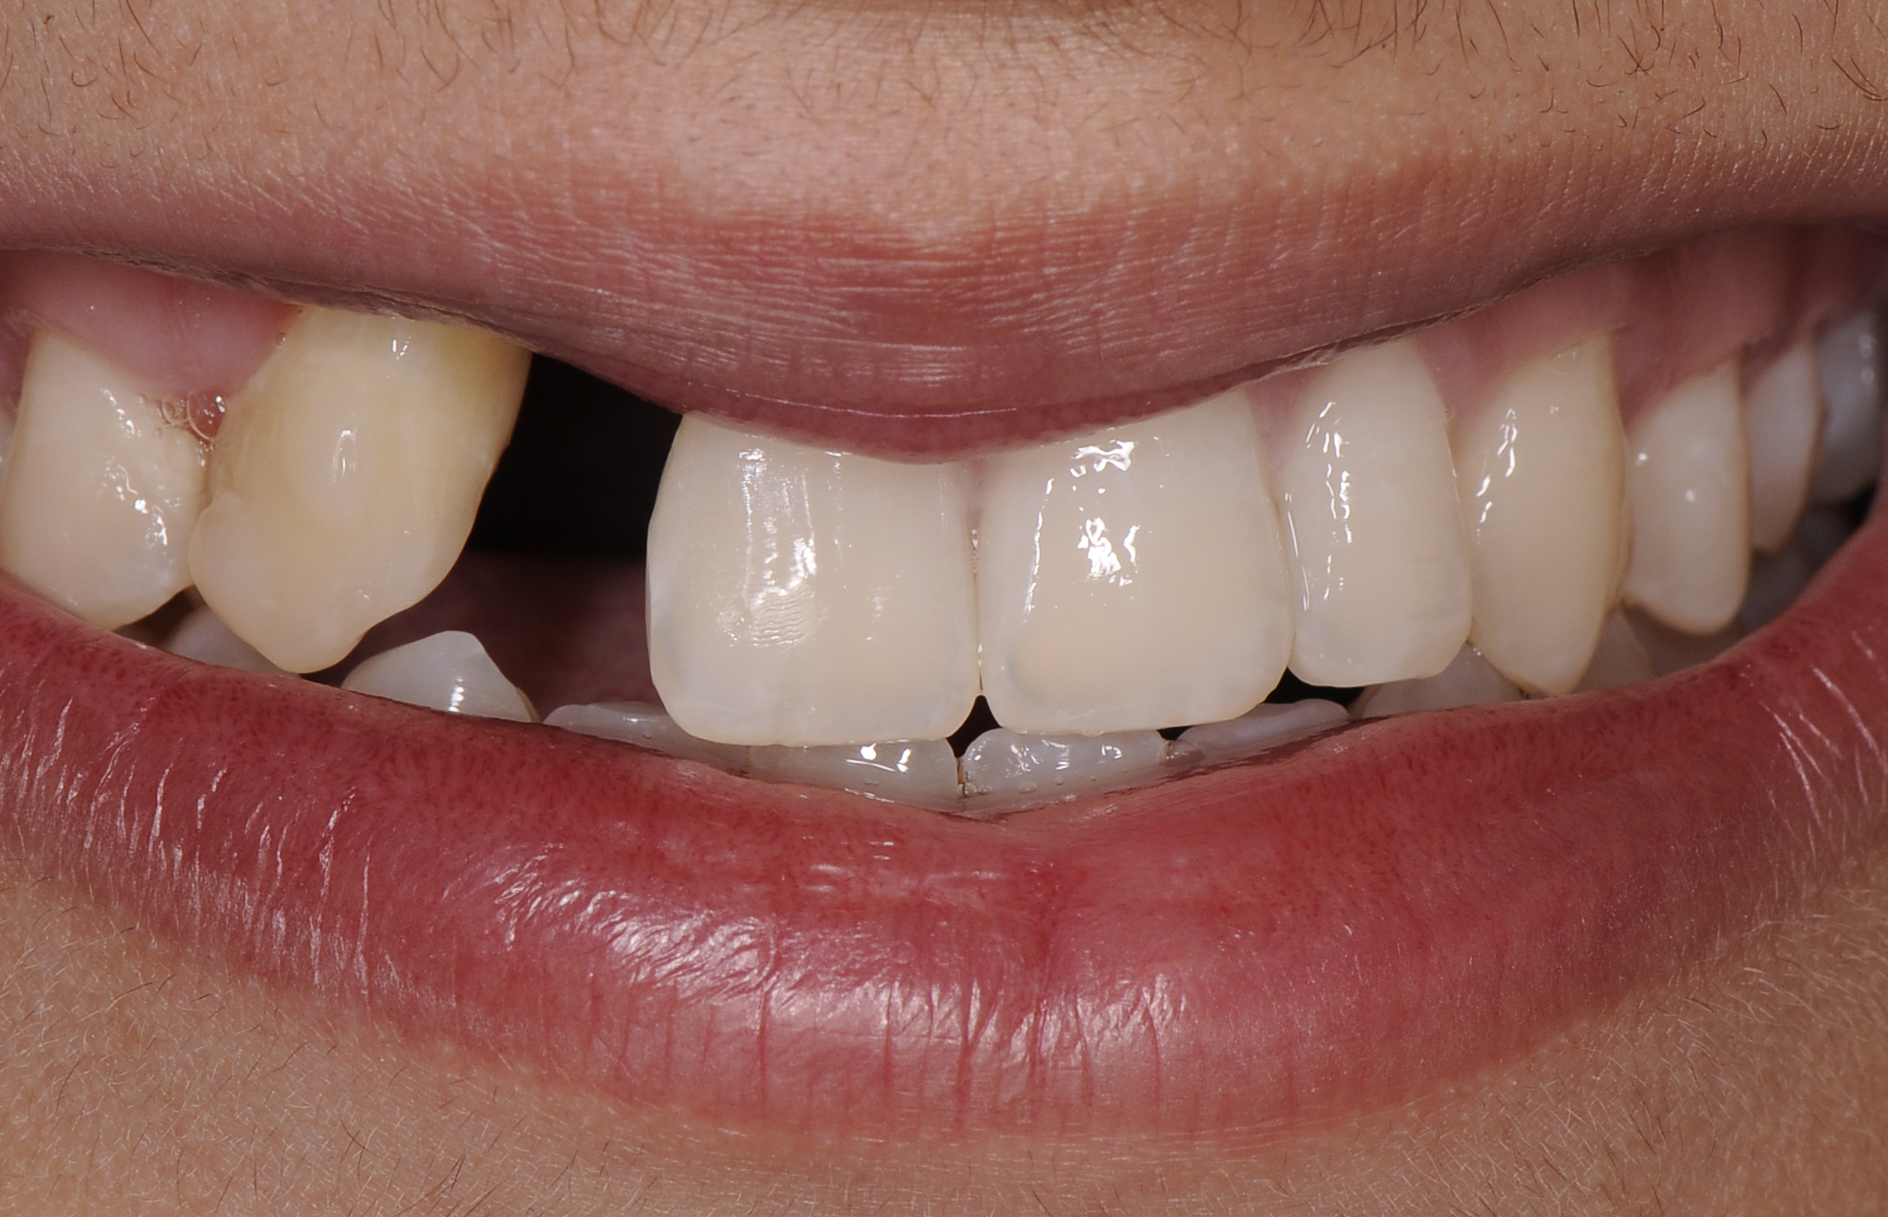

A healthy 20-year-old woman presented to the author’s office requesting treatment for a large defect in the area of missing tooth No. 7. She exhibited a high smile line that revealed a clearly visible deformity, associated with pain and sensitivity on teeth Nos. 6 and 8 and in the area of tooth No. 7 (Figure 1). Although the patient wore a modified Essix retainer, the defect was still visible because of the magnitude of tissue loss and the revealing nature of her smile.

The patient reported previous comprehensive orthodontic therapy, part of which included the creation of adequate space for replacement of the congenitally missing maxillary right lateral incisor. After completion of orthodontic therapy, implant placement and bone grafting were performed in the area of No. 7. Unfortunately, both procedures failed, resulting in a large hard- and soft-tissue defect. A subsequent attempt to perform bone augmentation was also unsuccessful and, instead, resulted in a larger deficit and increased recession on teeth Nos. 6 and 8. After a recommendation to attempt a third bone graft, the patient decided to seek alternative options.